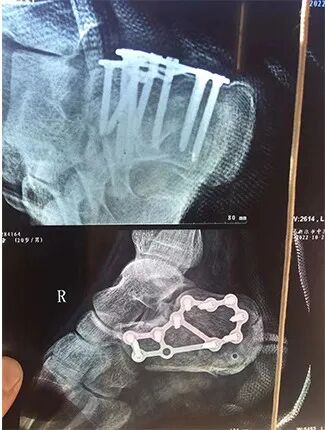

骨骼被多根钢钉固定

父亲闫立波和获救孩子的家人连忙打车送他去医院检查经诊断闫单童右脚足跟粉碎性骨折手术足足进行了3个小时

刀口超过10厘米脚跟被植入多根钢钉固定虽然很长时间不能下地行走但他表示一点儿也不后悔“孩子的家人多次来看我得知孩子已经脱离了危险我特别开心”